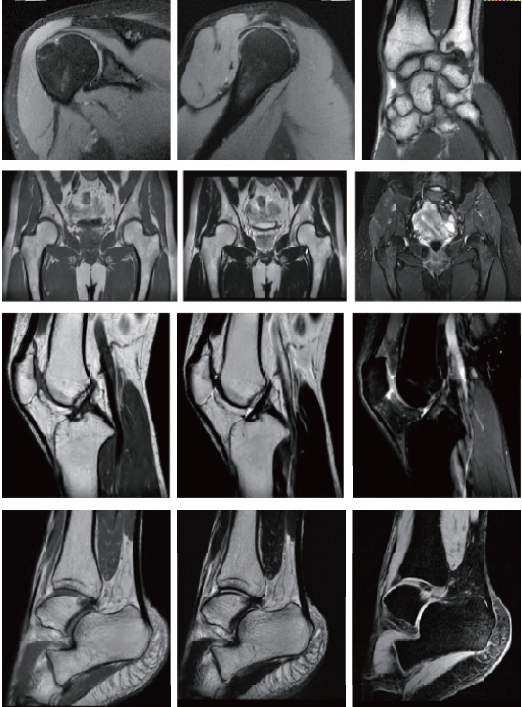

臨床畫(huà)廊